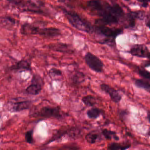

The idea of building a filter is to train a SVM to classify histopathologic images (HI) as relevant or irrelevant as illustrated in Fig. 1. For such an aim, we use the CRC dataset which is composed of images of 150150 pixels labeled according to the structure they contain. Eight types of structures are labeled: Tumor (T), Stroma (S), Complex Stroma (CS), Immune or lymphoid cells (L), Debris (D), Mucosa (M), Adipose (AD), and Background or Empty (E). The total number of images is 625 per structure/tissue type, resulting in 5,000 images. Fig. 2 depicts examples of the images from the dataset.

| (a) Adipose | (b) Complex Stroma | (c) Debris | (d) Empty |

| (e) Lympho | (f) Mucosa | (g) Stroma | (h) Tumor |